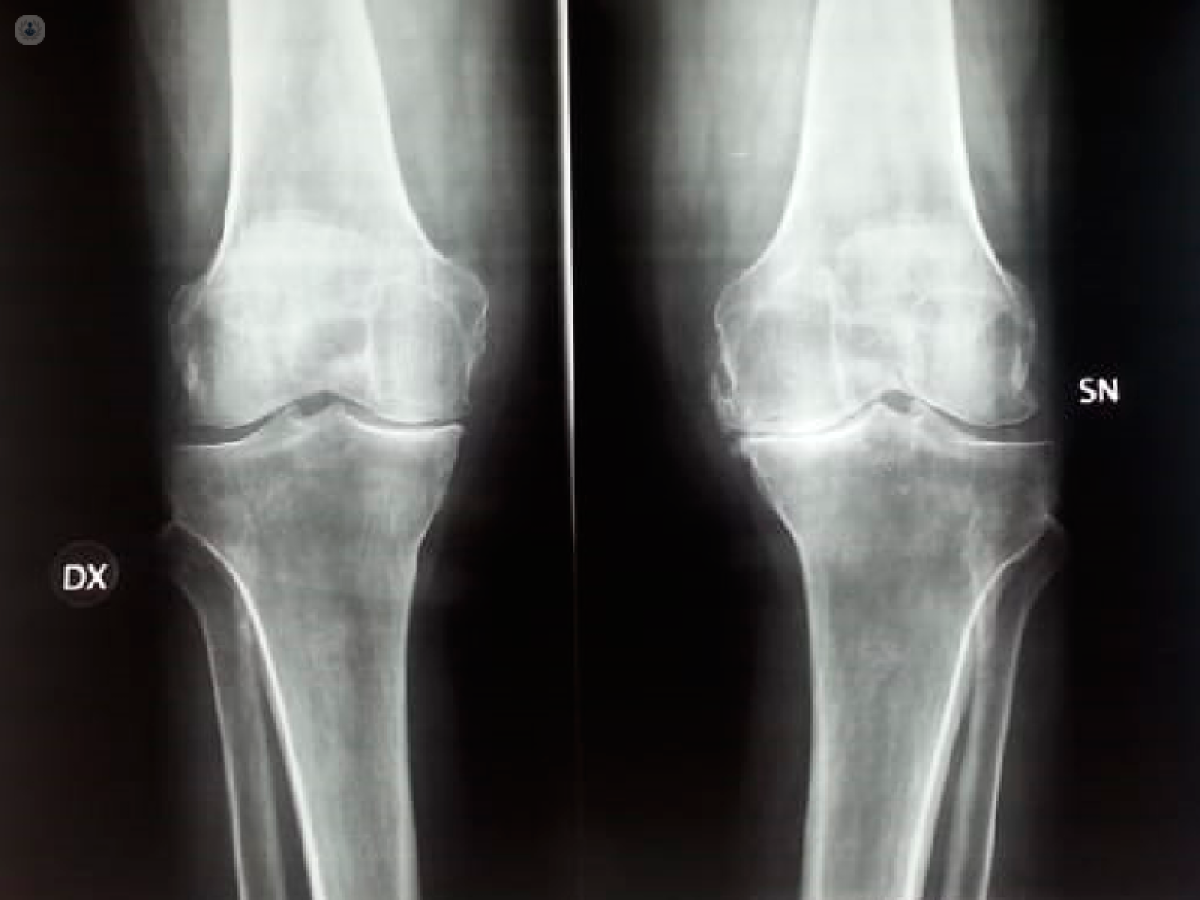

Gonartrosi o artrosi del ginocchio

L’artrosi del ginocchio, chiamata anche gonartrosi, è una patologia sempre più diffusa, si manifesta in età avanzata, ma non solo, spesso si presenta anche in giovane età.

La gonartrosi è causata dal progressivo indebolimento della cartilagine articolare, un elemento fondamentale per tutti i nostri movimenti, che porta, successivamente, al deterioramento delle altre componenti del ginocchio, come i legamenti, i menischi, i tendini e l’osso subcondrale.